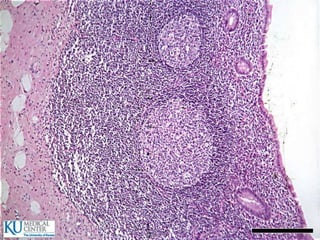

 El tercio posterior de la lengua tiene nódulos linfáticos

Lengua  El tercioposterior de la lengua tiene nódulos linfáticos  Criptas  Papilas:  Filiformes  Fungiformes  Circunvaladas  Foliadas